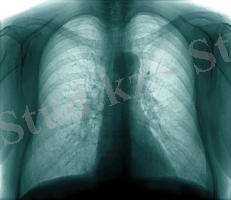

Кеуде ішілік лимфа түйіндерінің туберкулезі- біріншілік туберкулездің ошақты клиникалық формасы, ол әдетте өкпе тінінде арнайы қабыну өзгерісінің дамуынсыз пайда болады. (8. 3. -ші сурет) .

Кеуде ішілік лимфа түйіндерінің зақымдану көлеміне байланысты және қабыну процессінің сипатына байланысты шартты түрде ауруды инфильтративті және тумарозды(ісік тәрізді) түрге бөледі. Инфильтративті формасында - перифокальды инфильтрация және айқын емес казеозды некрозбен жүретін лимфа түйіндеріндегі гиперпластикалық реакция. Тумарозды формасын лимфа түйініндегі айқын казеозды некрозбен және оны қоршаған тіндердегі әлсіз инфильтративті реакциямен ассоциациялайды.

Кеуде ішілік лимфа түйіндері туберкулезінің асқынбаған ағымы жиі қолайлы, әсіресе оның ерте диагностикасында және уақтылы бастаған емінде.

Перифокальды инфильтрация сорылып, казеозды массаның орнына кальцинат түзіледі, лимфа түйінінің капсуласы гиализденеді, фиброзды өзгеріс дамиды. Бұл процесстер баяу жүреді. Ауру басталғаннан орташа 2-3 жылдан соң ауруға тән қалдықты өзгерістер клиникалық жазылумен аяқталады.